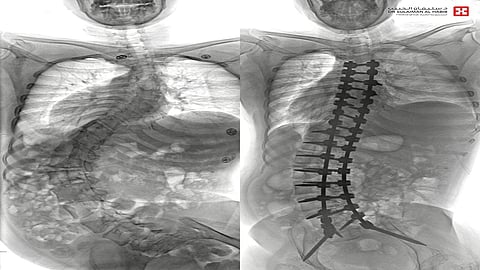

وقال د. "خليفة"؛ إن السيدة راجعت المستشفى، وهي بحالة صحية معقدة، إذ كانت تجد صعوبة بالغة في الحركة والجلوس، وعدم القدرة على أداء مهامها الحياتية، إلا بمعاونة الأهل، وأجرت عدة فحوصات دقيقة، حيث أظهرت صور الأشعة إصابتها بحالة انحراف "جنف" عالٍ فوق الـ" 80 درجة وميلان كبير بالورك، وبعد دراسة الحالة، انتهى الفريق الطبي إلى ضرورة التدخُّل الجراحي للحد من المضاعفات، وبعد اتخاذ التدابير اللازمة، أخضعت لعملية جراحية، تمّ فيها تقويم العمود الفقري بعدد "30" من البراغي المعدنية من التايتانيوم، وتثبيت ودمج الفقرات، واستخدمت في العملية التي استمرت 8 ساعات، مجموعة من أحدث الأجهزة التي أسهمت مع الكوادر الطبية عالية الكفاءة والتأهيل بالمستشفى، ولله الحمد، في إنجاحها.

وبقيت المراجعة منوّمة قيد العناية الطبية الحثيثة بالمستشفى لعدة أيام، تقدّمت خلالها حالتها الصحية باطراد، إذ تحسّن وضع الجلوس واستقامة الظهر بشكلٍ لافت، وكذلك قدرتها على الاستلقاء والنوم على ظهرها، عقب تعديل وضعية الحوض والكتف، وبعد عدة أشهر راجعت السيدة المستشفى للمتابعة، وهي في أتم الصحة والعافية، حيث استقام الجلوس بشكلٍ مذهلٍ والتحم العظم، وبدأت بالبرنامج التأهيلي المقرر لها اعتماداً على طرفها الأعلى، حيث سُمح لها بالسباحة وتقوية عضلات الظهر والطرف العلوي.